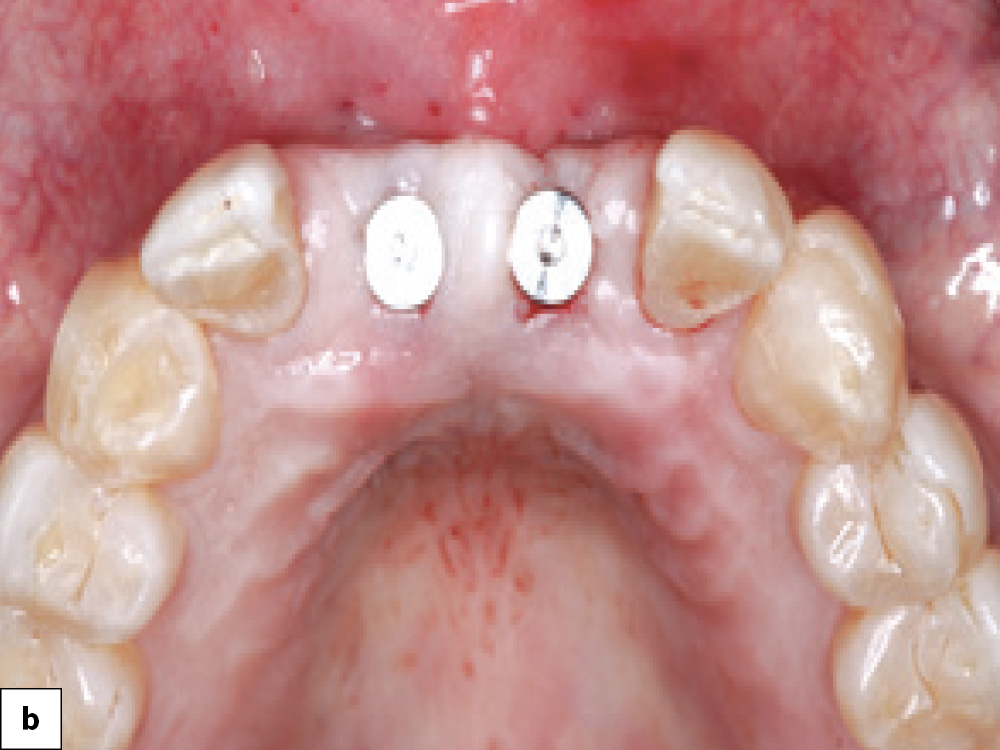

Two-stage Technique Cover Screw Connection

One-stage Technique Abutment Placed

Temporary Crown Provisionalization

Surgical site closure options: (a) Two-stage technique, in which a cover screw is connected to the implant before suturing the soft-tissue flap; (b) One-stage technique, in which a healing abutment is placed; (c) Immediate provisionalization with a temporary crown.